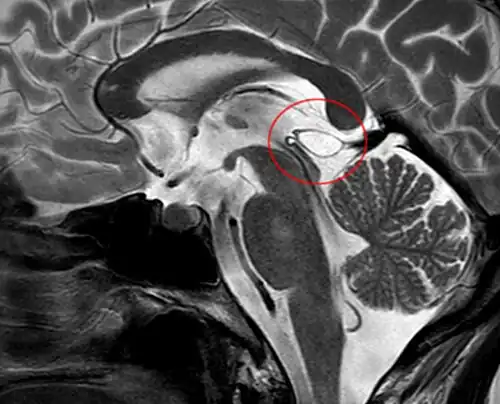

Pineal gland cyst

A pineal gland cyst is a usually benign (non-malignant) cyst in the pineal gland, a small endocrine gland in the brain. Historically, these fluid-filled bodies appeared on 1-4% of magnetic resonance imaging (MRI) brain scans, but were more frequently diagnosed at death, seen in 4-11% of autopsies.[1] A 2007 study by Pu et al. found a frequency of 23% in brain scans (with a mean diameter of 4.3 mm).[1]

The National Organization for Rare Disorders states that pineal cysts larger than 5.0 mm are "rare findings" and are possibly symptomatic. If narrowing of the cerebral aqueduct occurs, many neurological symptoms may exist, including headaches, vertigo, nausea, muscle fasciculations, eye sensitivity, and ataxia. Continued monitoring of the cyst might be recommended to monitor its growth, and surgery may be necessary.[2]